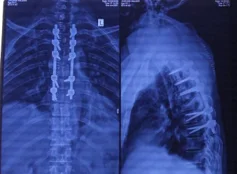

Before & After Clinical Gallery

We showcase real patient cases (with consent), including:

- Pre- and Post-operative MRIs and X-rays

- Disc Herniations, Stenosis, and Spondylolisthesis cases

- Visible improvement in alignment and decompression